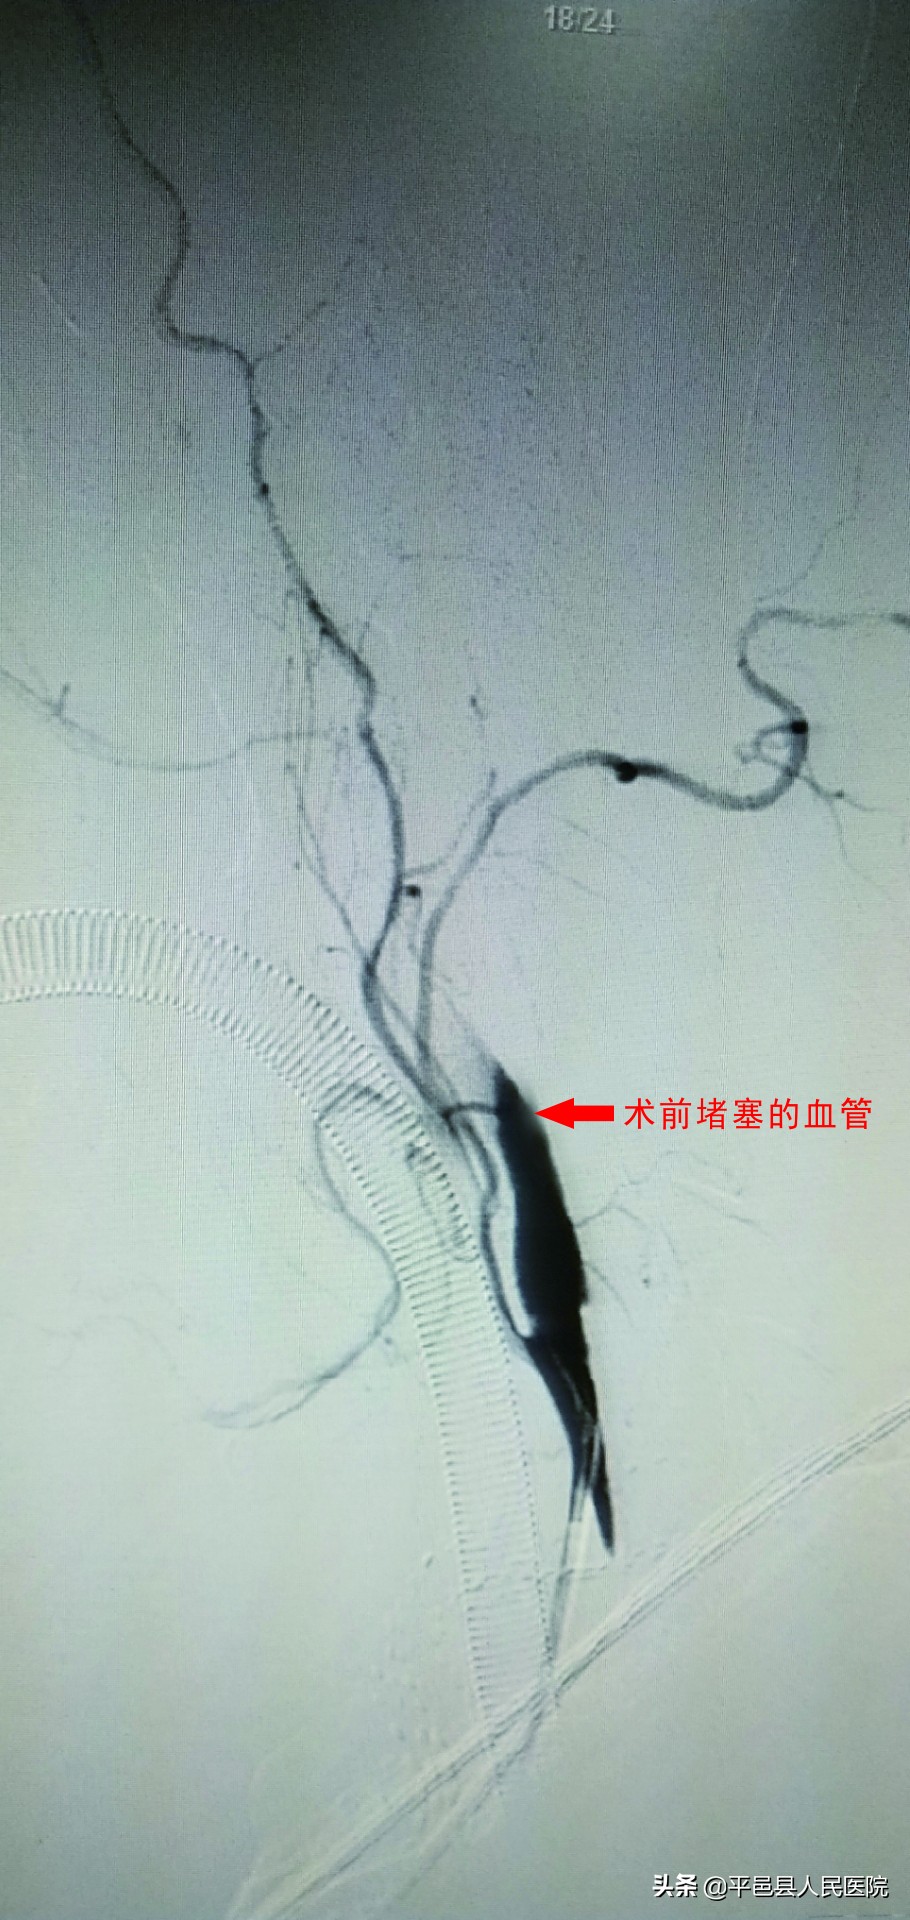

5月7日上午10:30左右,在平邑县人民医院急诊科因头晕不适住院治疗的吴女士,突发烦躁、左侧肢体无力。经过必要检查、综合评估,考虑患者为急性脑梗死,建议药物溶栓。10:45即开始阿替普酶静脉溶栓治疗,考虑患者神经功能缺损症状符合急性前循环大血管栓塞,静脉溶栓再通率低,应桥接机械取栓治疗,通知神经介入小组待命,患者11:45结束溶栓时症状无明显改善,急查颅脑磁共振示右侧基底节急性小片梗死,磁共振血管成像示右侧大脑中动脉完全闭塞,大动脉栓塞诊断明确,如不紧急取栓,梗死面积很快会扩大至整个右侧大脑半球,患者生命危险极大。与患者家属充分沟通后,立即准备桥接介入取栓。

被堵塞的血管

患者在医护人员密切监护下被送至导管室,全麻后开始手术。主动脉弓上及双侧颈动脉造影示右侧颈内动脉明显慢血流,造影剂充盈颈内动脉C6段,左侧颈内动脉通过前交通动脉向右侧大脑前动脉代偿供血,未见有其他血管代偿右侧大脑动脉供血区,立即构建取栓路径,微导管+微导丝小心到达栓塞部位,此时患者突发室性心动过速,继而很快出现发作性室颤两次,手术医师立即停止取栓操作,静脉推注盐酸利多卡因,急请心内科医师前来会诊,经积极处置,10分钟后患者心律逐渐恢复正常,确定患者排除风险后继续手术操作。经过取栓支架拉栓和抽吸取栓,病变血管完全再通,达mTICI 3级血流再通,手术取得圆满成功。5月8日下午术后24小时再次复查CT,仅有少量脑内梗死病灶散在于大脑中动脉供血区,患者意识恢复,偏瘫侧肢体肌力部分恢复,现患者正在接受康复锻炼。